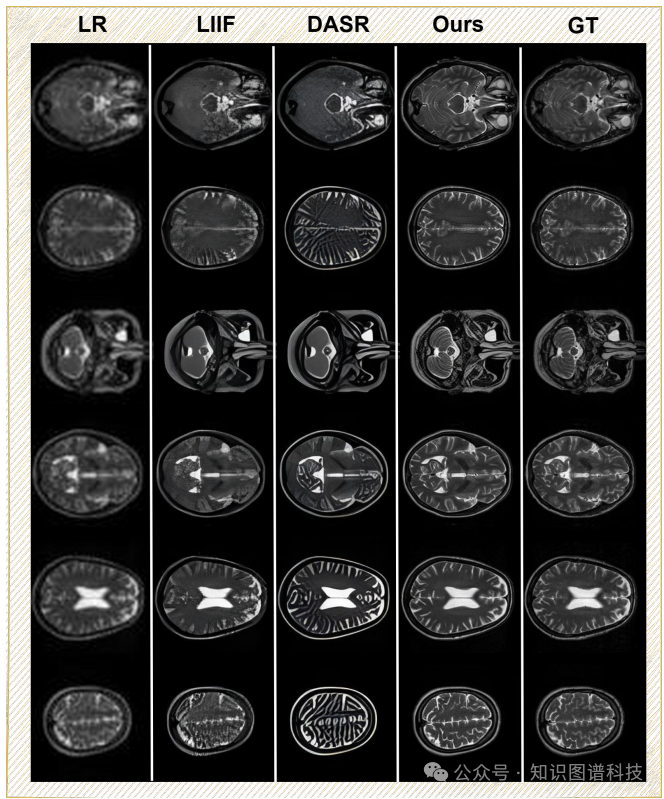

超分辨率:在IXI数据集上的4倍超分辨率实验中,HealthGPT-M3在SSIM、PSNR和MSE指标上均表现优异。